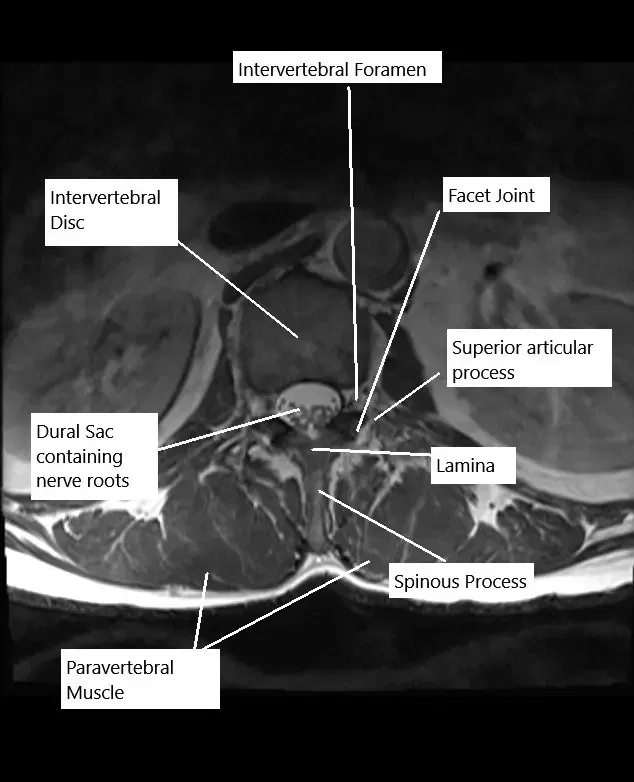

La columna lumbar consta de cinco vértebras (L1-L5) y discos intervertebrales que separan cada vértebra. La médula espinal pasa por el canal espinal y los nervios espinales salen por aberturas llamadas forámenes. Estos nervios controlan la sensibilidad y el movimiento en la parte inferior del cuerpo, incluyendo las piernas, los pies y la pelvis. Cuando los discos se hernian o el canal espinal se estrecha, puede comprimir las raíces nerviosas, lo que provoca dolor y pérdida de función.

- RM: La técnica de imagen más útil para identificar hernias discales, estenosis espinal y compresión nerviosa.